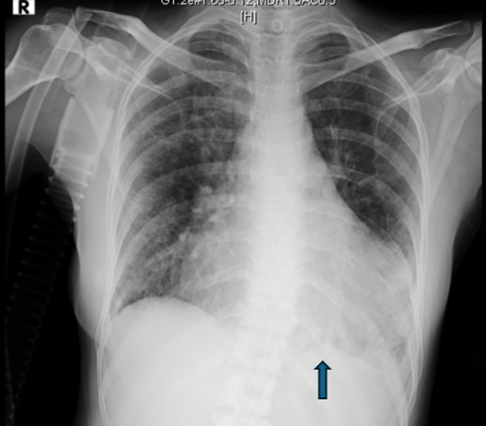

Posteroanterior chest radiograph showed cardiomegaly without any lung lesion. (Figure 1) An emergent ECHO cardiogram showed moderate Pericardial effusion (posteriorly 17mm, anteriorly 4mm, laterally 6mm) There was no RA/RV diastolic collapse seen. (Figure 2)

Figure 1: chest radiograph showing cardiomegaly without any lung lesion.